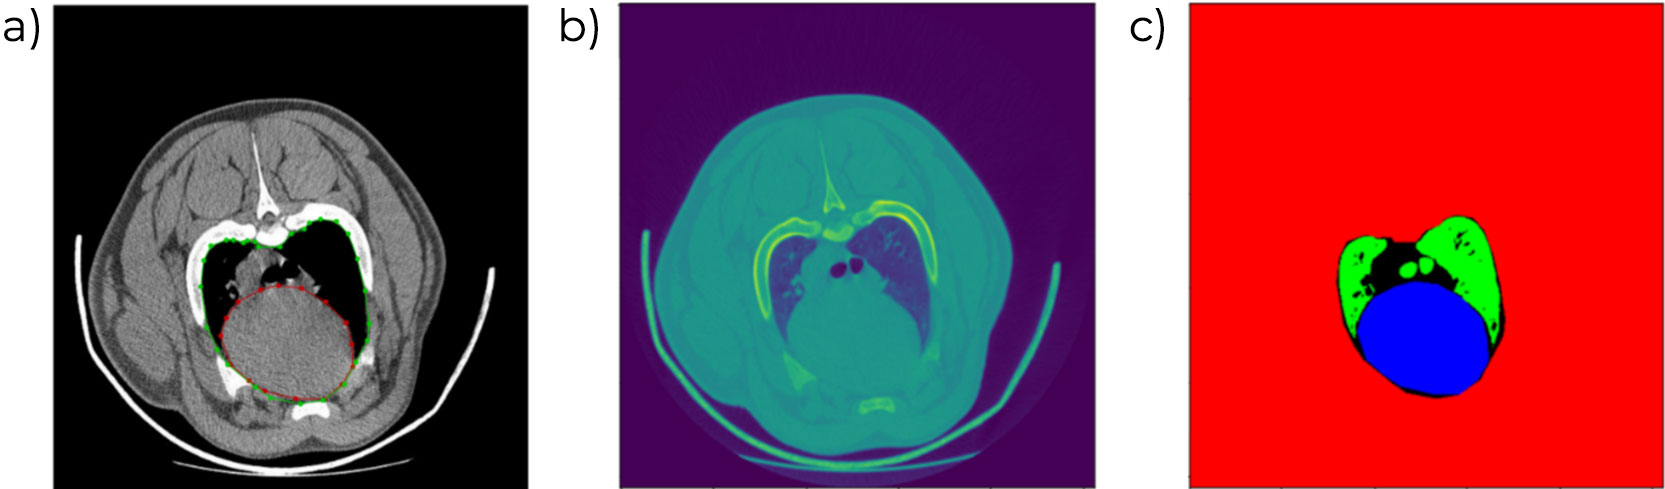

La presencia de lesiones en la cabeza del fémur y húmero para identificar procesos de artritis u osteocondrosis. Esta valoración forma parte del objetivo de selección de todas las líneas. El proceso incluye una parte manual que será próximamente reemplazada por un proceso automatizado de segmentación y cuantificación de las lesiones que permitirá, además, incluir la evaluación de más superficies óseas.

El tamaño y forma de la escápula se han evaluado y relacionado con la longevidad de las cerdas y la presencia de úlceras y otras lesiones en la paleta de cerdas adultas.

Otros fenotipos que podrían ser de interés: En la actualidad se investiga para desarrollar nuevos fenotipos relacionados con las vísceras de los cerdos, tales como el volumen de órganos como el corazón y los pulmones, que podrían guardar relación con la robustez de los animales y su tolerancia al estrés. Sin embargo, la automatización de estos fenotipos plantea retos adicionales pues estos órganos tienen un comportamiento dinámico cambiando de forma y tamaño con la respiración y el latido y eso complica el proceso de análisis automático. Actualmente se está investigando, en cooperación con la Facultad de Veterinaria de la Universidad NMBU (Noruega) para integrar la información de la TC e información recogida mediante electrocardiografía (ECG).